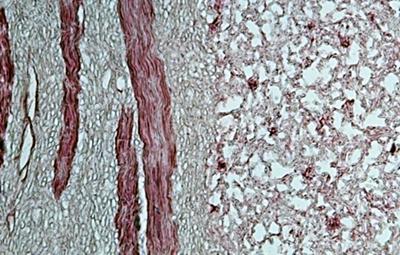

我将冬虫夏草制成切片,到显微镜下观察一下。(见图3、图4)

图4:红色是虫体的肌肉(平滑肌),浅蓝色竹节样细丝是霉菌菌丝